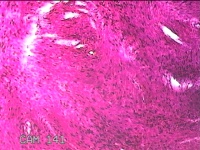

子宫肌瘤

性别

女

年龄

41岁

临床诊断

子宫肌壁间肌瘤

一般病史

发现子宫肌瘤4年余。

标本名称

大体所见

灰白色圆柱形条索状组织10.5x7x1.3㎝一堆,切面均为灰白色结节状或编织状,质硬。

图3